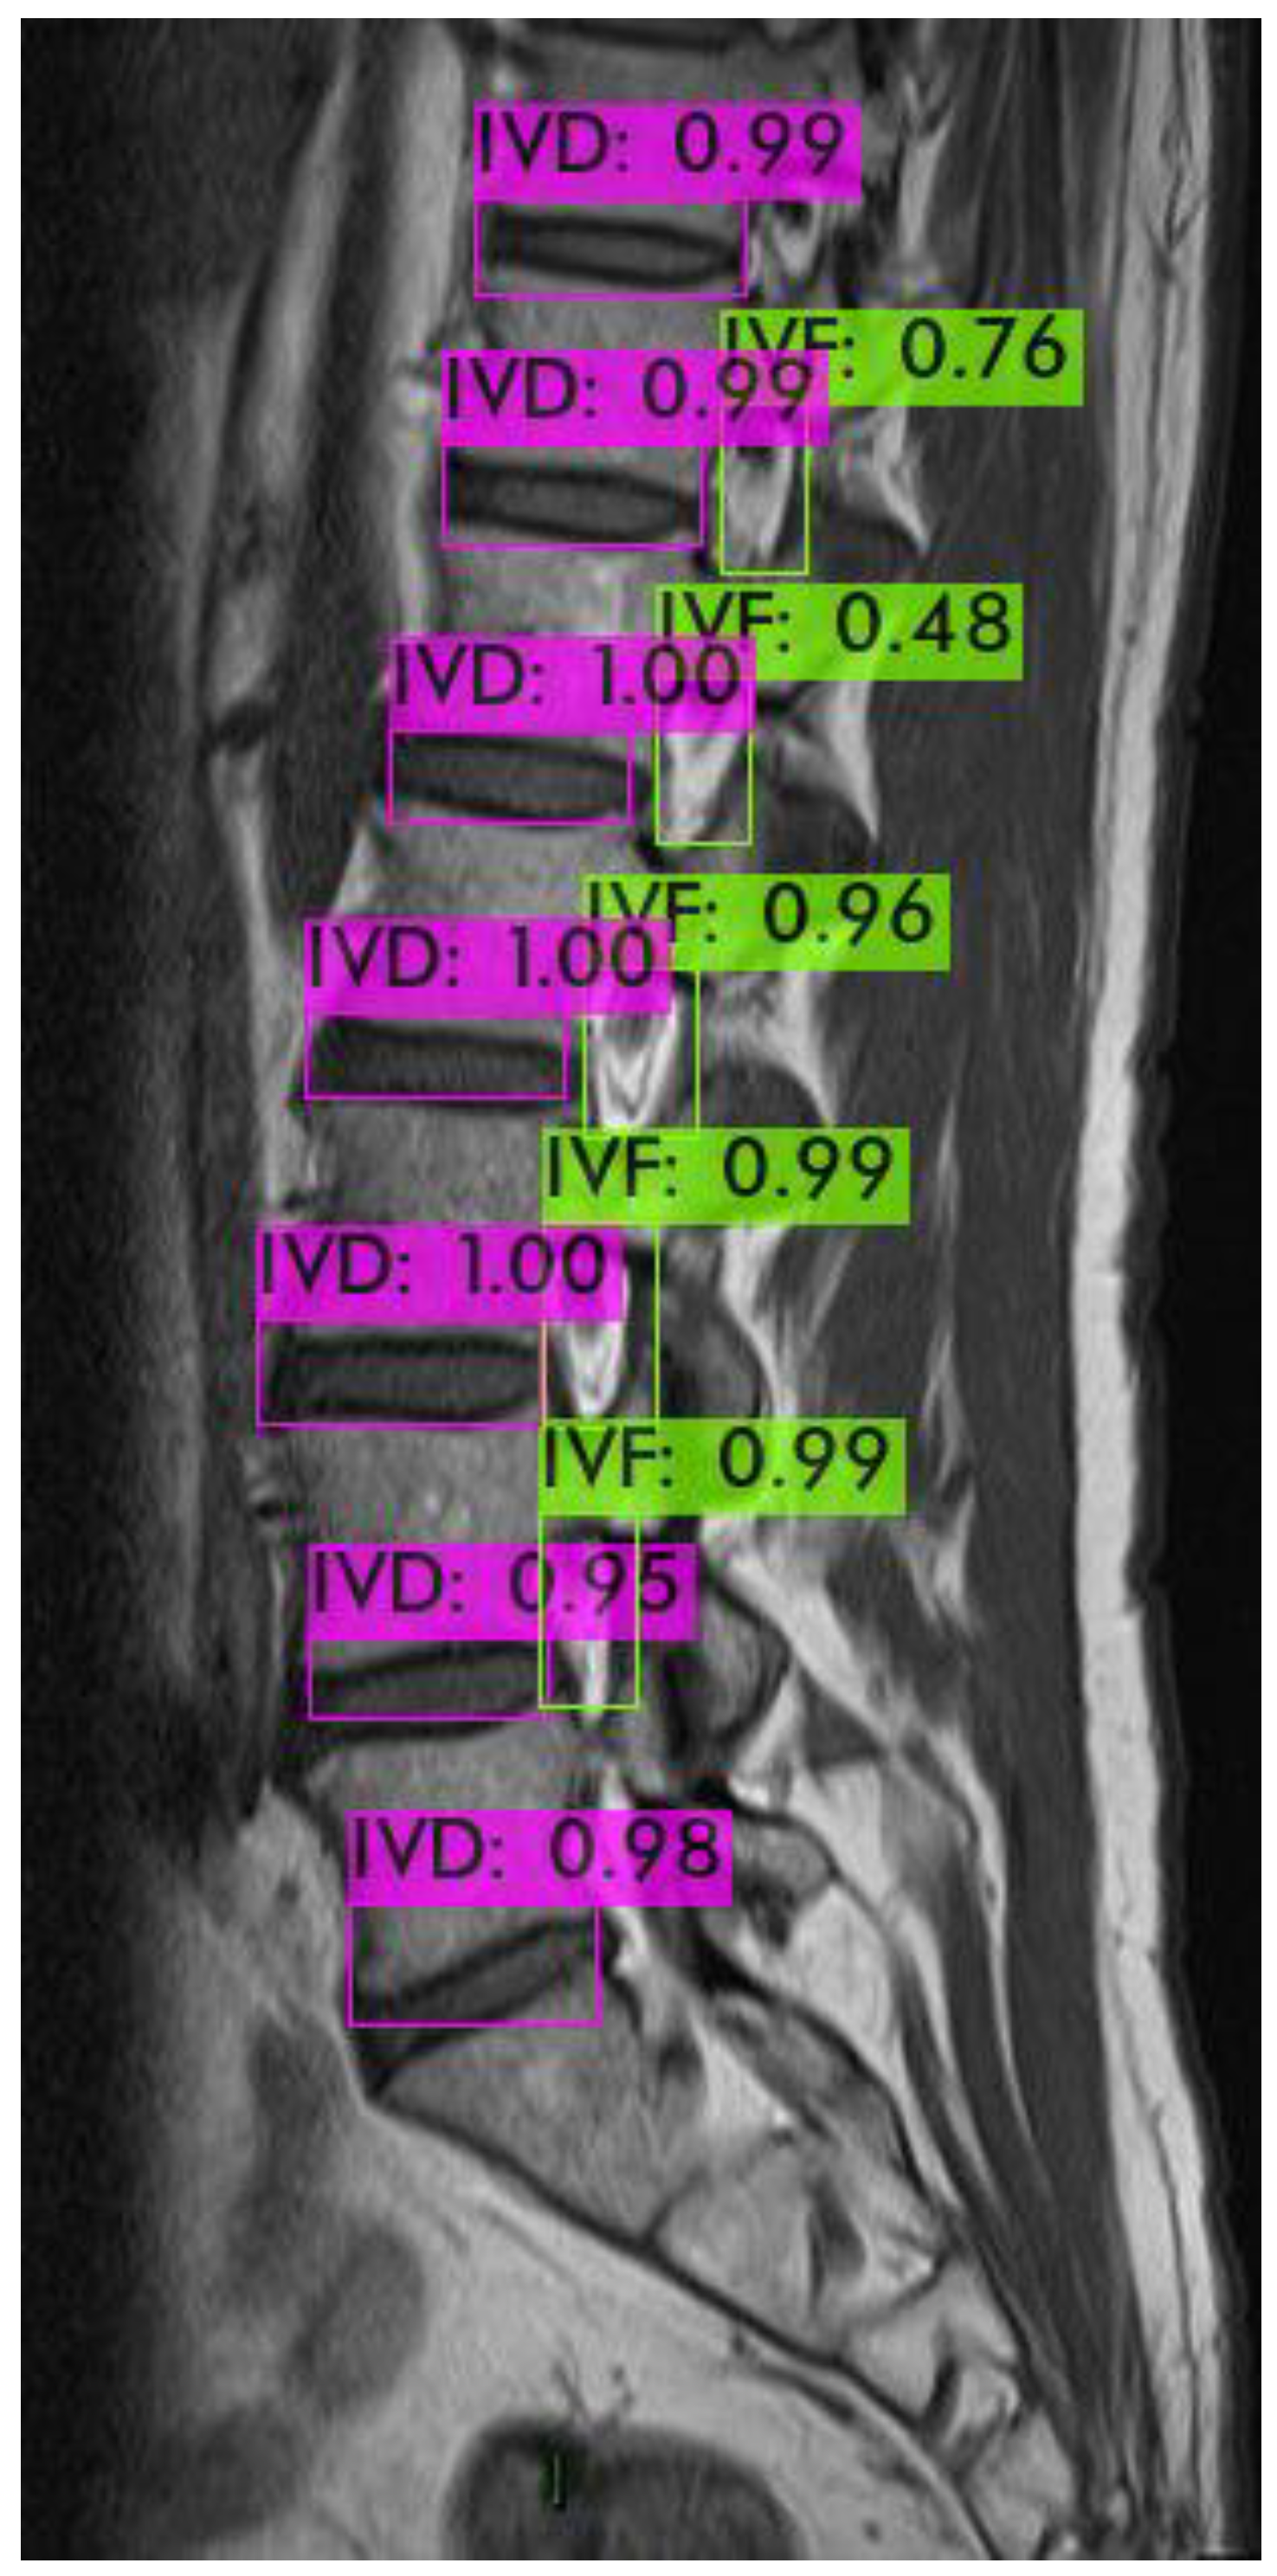

For identifying the area of the intervertebral foramen (IVF) and intervertebral disc (IVD), we first employ the YOLOv4 object detection model to detect the intervertebral foramen in MRI images shown in Figure 8. The detected foramen is then cropped into sub-images, which are further processed using DL methods to segment the areas of the IVF and IVD within these sub-images. After segmentation, the number of pixels occupied by the intervertebral foramen in the MRI dataset is analyzed. Finally, by using the Field of View (FOV), detailed information from the MRI dataset, this pixel count is converted into an actual area measurement in square millimeters.

Figure 8. YOLOv4 object detection.